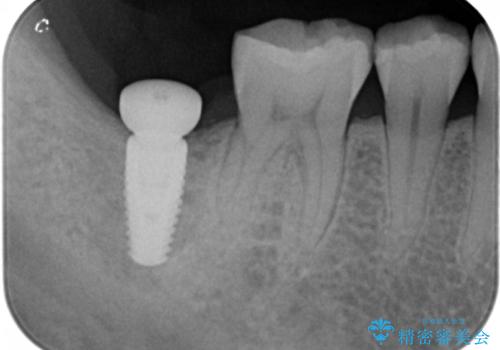

奥歯の歯ぐきからウミが出る 抜歯してインプラントへ

- 奥歯の歯ぐきからウミが出ている、抜歯が必要と他院で言われたとのことでした。

ただし、かかりつけではインプラント治療を行っていないため、病院を探したとのことでした。

抜歯を行い、インプラントを入れていきました。

炎症で骨が少なかった場所には骨補填材を置いています。

高さがないため、スクリューリテインのインプラントの上部構造にしています。